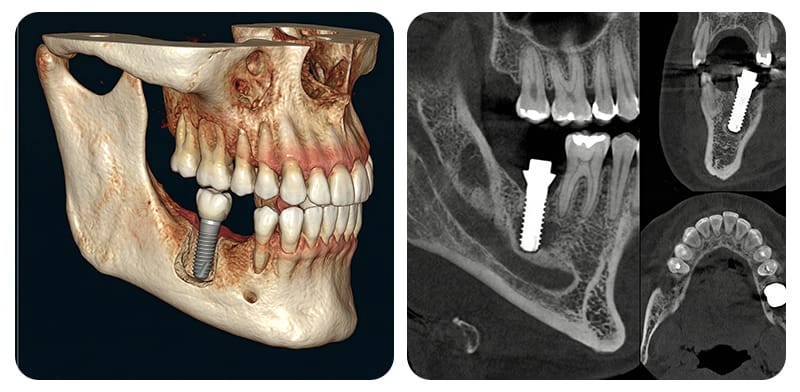

下顎の奥歯の部位は、下歯槽神経管という重要な神経と血管の複合体が通る道です。この神経管と埋入位置が近すぎると、痺れや感覚低下などの異常症状が発生する可能性があるため、骨の立体的な状態を綿密に分析する診断過程が何よりも重要です。

通常、パノラマや口腔内レントゲンなどの2D画像でおおよ上の経路をまず確認した後、神経管の位置が不明確な場合や断面情報がさらに必要な場合に、CBCT撮影をトリアージ(選択的に追加)します。確保された3次元立体画像を通じて、神経管の走行経路や変異を確認し、保守的な安全マージンを設定します。

文献では、神経管との安全マージン(Safety margin)として2mmという距離が頻繁に言及されますが、この数値だけで感覚異常が完全に防げると断定することは困難です。